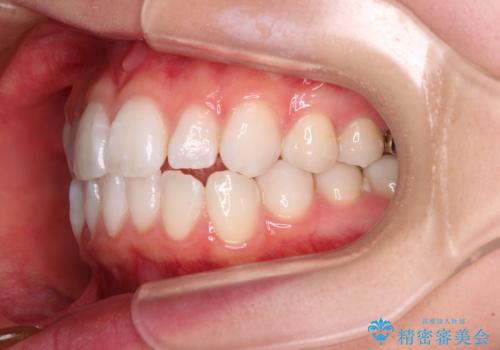

4本の歯を抜歯したことで、飛び出していた口元が引っ込み、横顔が大きく改善されました。

- 前歯の出っ歯と口元の閉じにくさを気にして来院された患者様です。

口元を積極的に引っ込めるために、上下左右の小臼歯4本を抜歯することとしました。